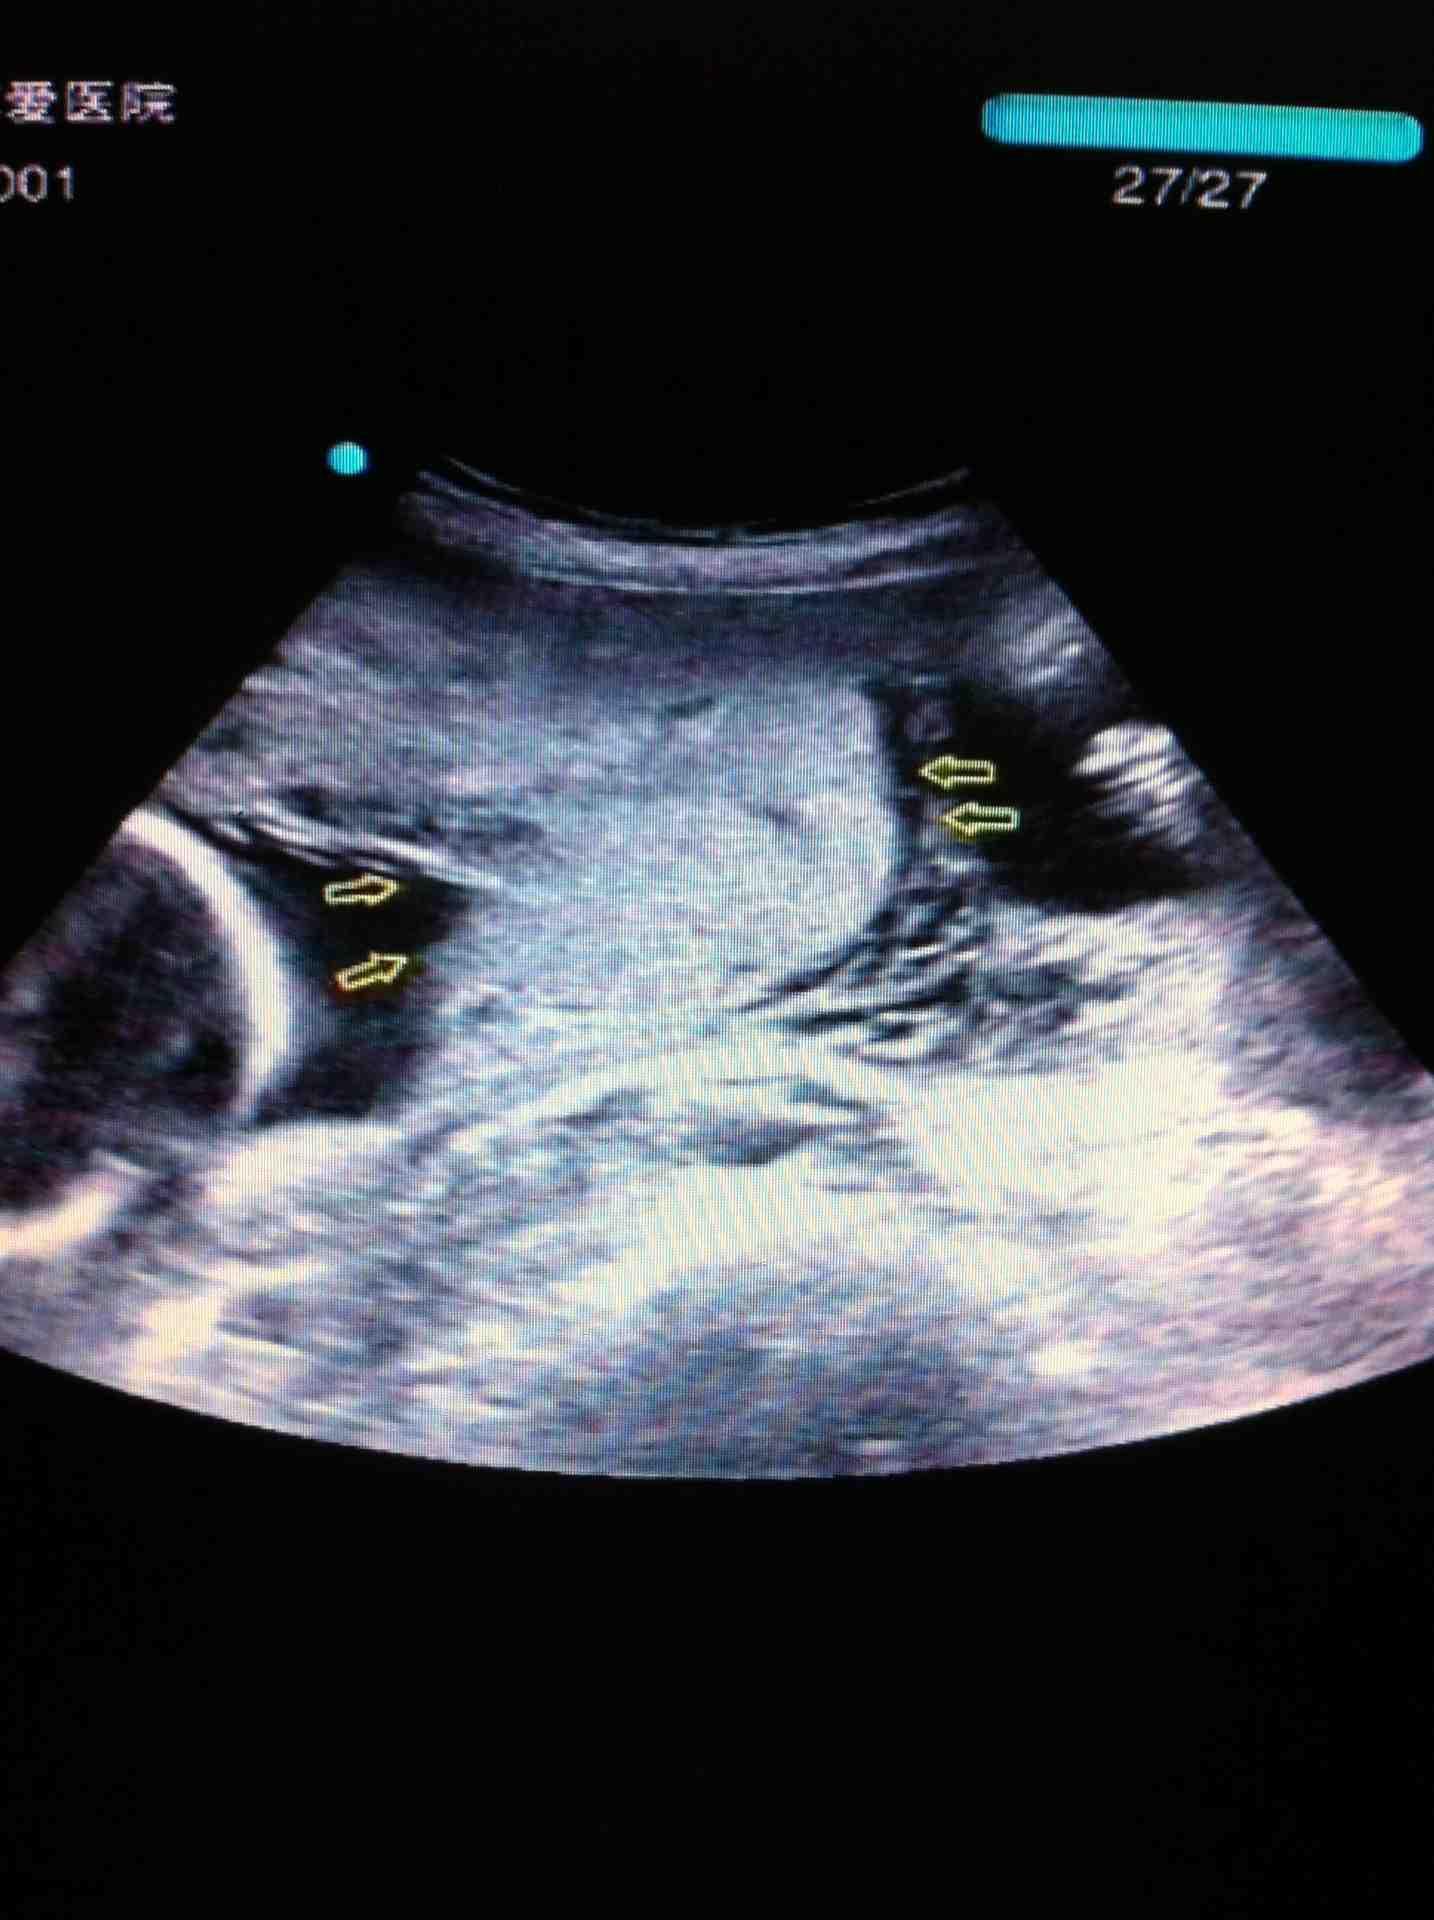

【病例分享】如此典型的轮状胎盘,看过一次就不会忘记_超声

图片尺寸768x576